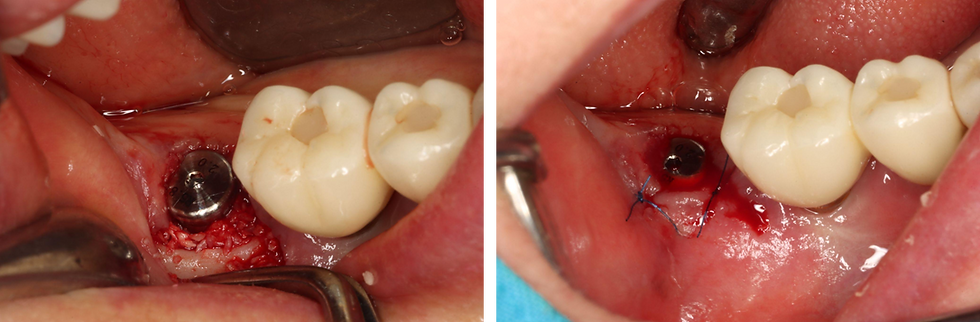

Even with just 2 mm of anchorage from ‘I’ fixation, the insertion torque reaches 40 Ncm.

The peri-implant gap is grafted with Neo Bone allograft and sutured.